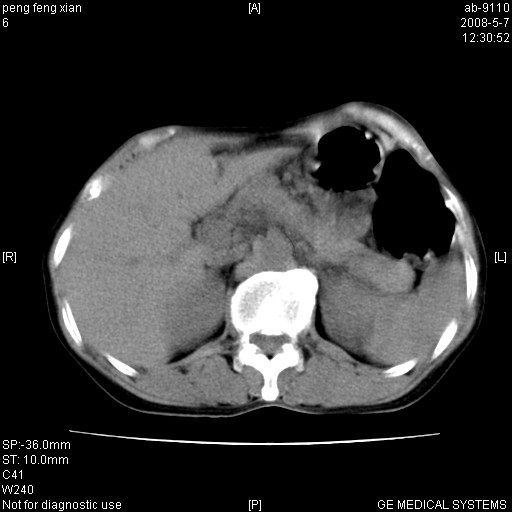

女,56岁。b超左一腹包块,考虑胃肠道肿瘤。

考虑为:胃肿瘤(胃癌?)。建议:行胃镜检查进一步明确诊断。

胃壁增厚,左前胸壁局限性隆起,考虑胃癌可能性大,建议做胃镜

典型胃癌胰体尾部受侵。

胃底占位待出;右肾结石?

胃体部胃壁增厚,不均匀性强化,与胰腺分解欠情.

考虑:胃癌,胰腺受侵待除外.

鉴别:胃淋巴瘤(强化不明显)

建议:胃镜检查.